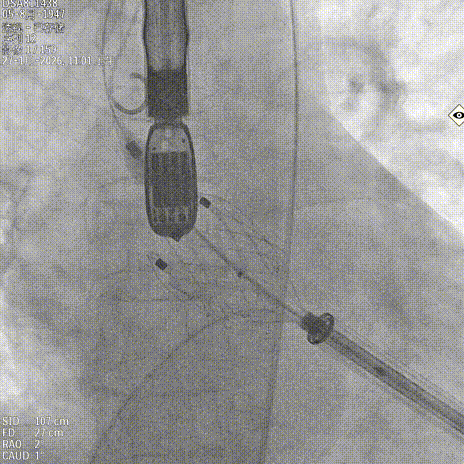

调整再次入窦

造影确认定位件入窦底

释放瓣膜

锁丝脱钩

撤出输送器

术后造影 反流消失